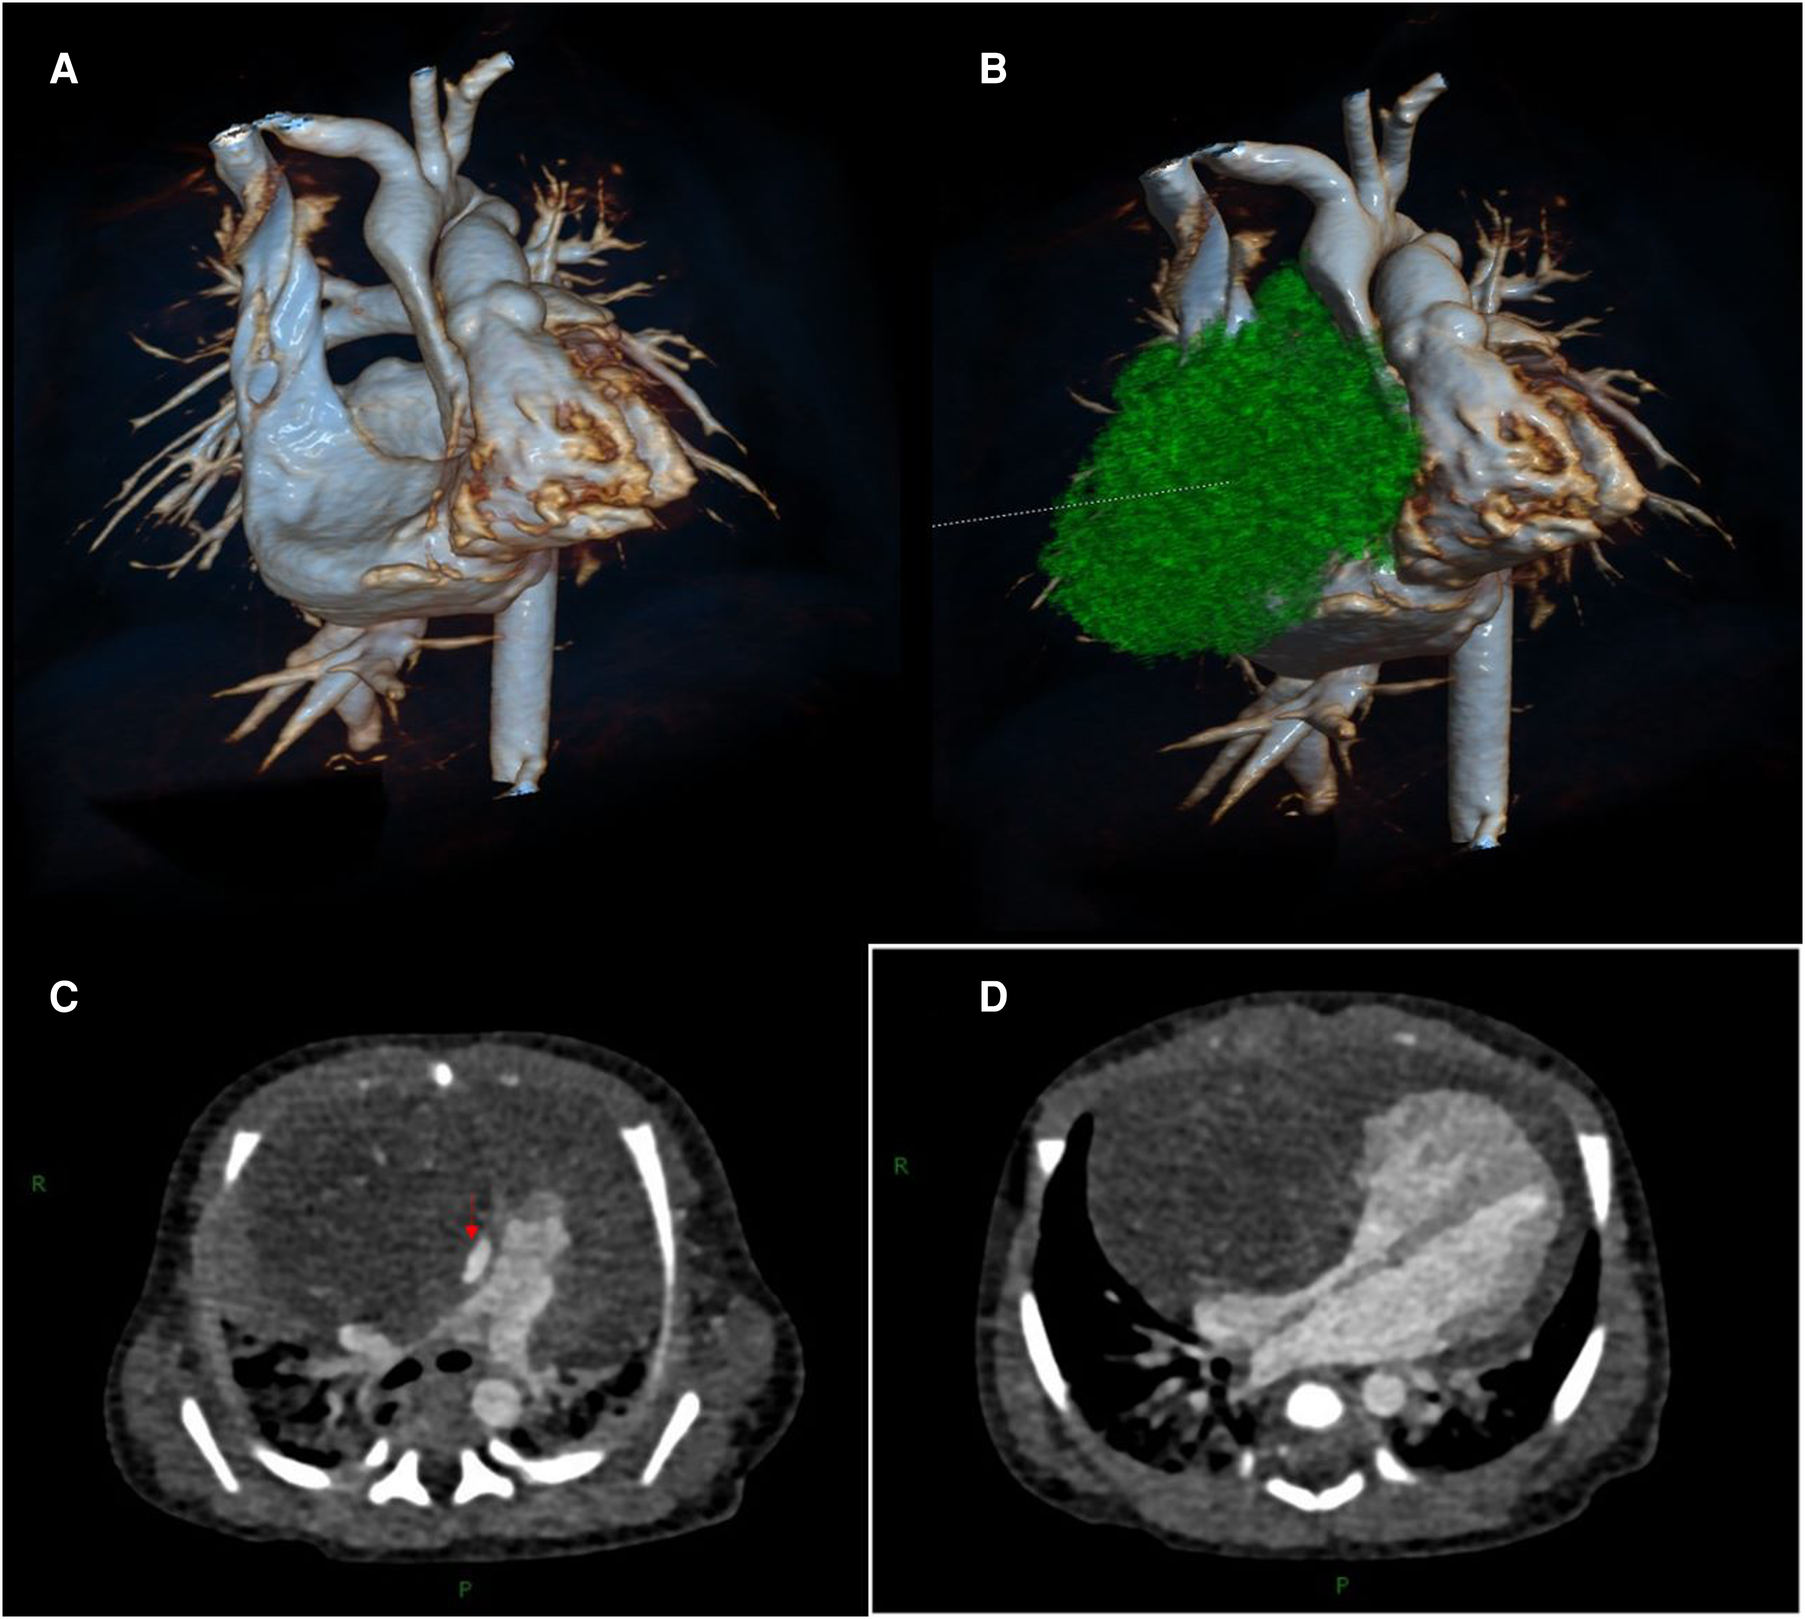

Transthoracic echocardiography (TTE) showed a slightly hyperechoic mass in the right pericardial cavity, approximately 40 × 37 mm in size (Figure 2). The mass was close to the bottom of the heart and was compressing the ascending aorta, with a clear boundary and uneven echo. Patent ductus arteriosus and atrial septal left-to-right small shunts were also observed. For better evaluation and confirmation of the diagnosis, cardiac computed tomography angiography (CTA) was performed, and a slightly low-density mass was seen outside the right atrium, with a size of approximately 44.3 × 39.2 × 42.3 mm (Figure 3). High-density strip calcifications were observed at the edge of the mass. There was an unclear boundary and mild enhancement of the lesion. There were multiple small blood vessel shadows inside, with blood supply originating from the ascending aorta (approximately 1.0 mm in diameter); the ascending aorta was evidently compressed and flattened, the heart was displaced to the left, and a large amount of pericardial effusion was seen. Chest CT scan revealed neonatal pneumonia.

Figure 3

Cardiac computed tomography angiography images. (A, B) Three-dimensional modeling images show a huge mass in the right front of the heart, which severely compresses the ascending aorta and right atrium. (C) The aorta (red arrow) is compressed and flattened by the mass. (D) The mass compresses the right atrium.